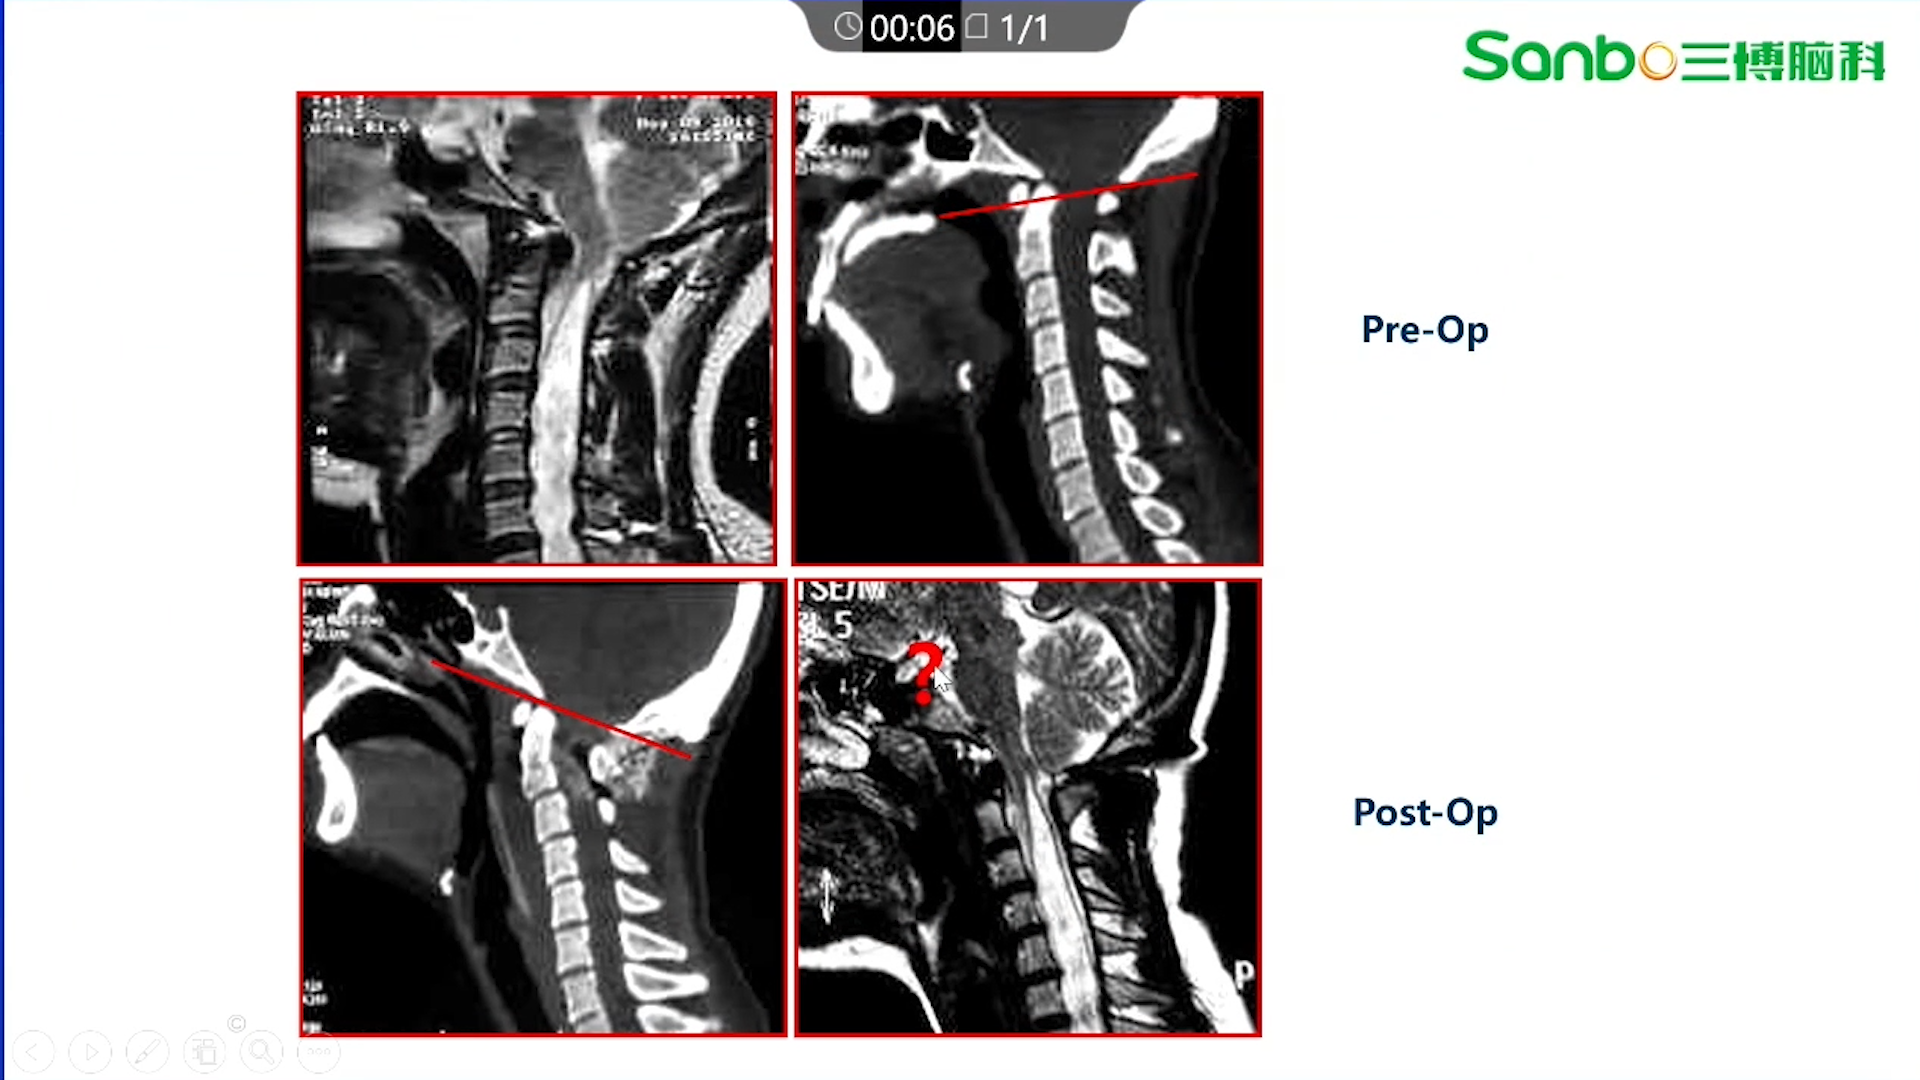

范涛教授:先天性颅底凹陷的分类及手术治疗

讲题先天性颅底凹陷的分类及手术治疗